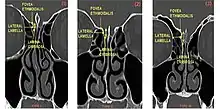

Keros classification

The Keros classification is a method of classifying the depth of the olfactory fossa.

The depth of the olfactory fossa is determined by the height of the lateral lamella of the cribriform plate. Keros in 1962, classified the depth into three categories.[3]

- type 1: has a depth of 1–3 mm (26.3% of population)

- type 2: has a depth of 4–7 mm (73.3% of population)

- type 3: has a depth of 8–16 mm (0.5% of population)

- type 4: has asymmetric depths (described by Stammberger)